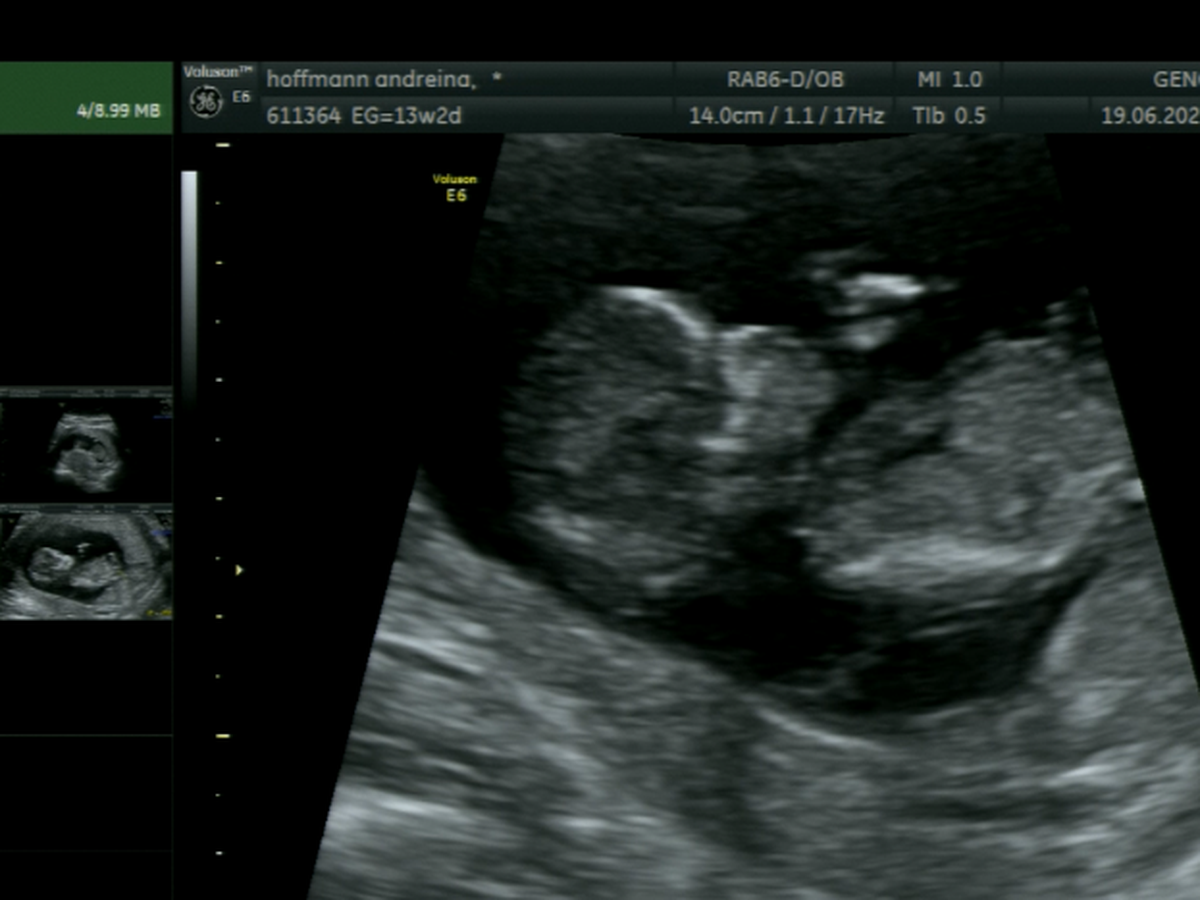

Hace poco me confirmaron que mi bebé, Constanza, tiene síndrome de Turner, una condición genética poco común que implica varios desafíos en su desarrollo. Además, se le detectó un higroma quístico y un derrame pleural, lo que complica aún más su situación y requiere controles médicos constantes y atención especializada.

Los médicos me aconsejaron interrumpir el embarazo… pero no pude hacerlo. En cada ecografía su corazoncito seguía latiendo con fuerza, y ahí entendí que ella está luchando por vivir. Yo tampoco me voy a rendir. Decidí seguir adelante, confiando en Dios, en la medicina y en el profundo amor que siento por ella.

Recently, I found out that my baby, Constanza, has Turner syndrome, a rare genetic condition that comes with several developmental challenges. She was also diagnosed with a cystic hygroma and pleural effusion, which further complicate her condition and require constant medical care and close monitoring.

Doctors advised me to terminate the pregnancy… but I couldn’t do it. At every ultrasound, her little heart was still beating strong, and I realized that she’s fighting to live. So I decided to fight with her. I chose to continue this journey with faith in God, in medicine, and in the deep love I already feel for her.